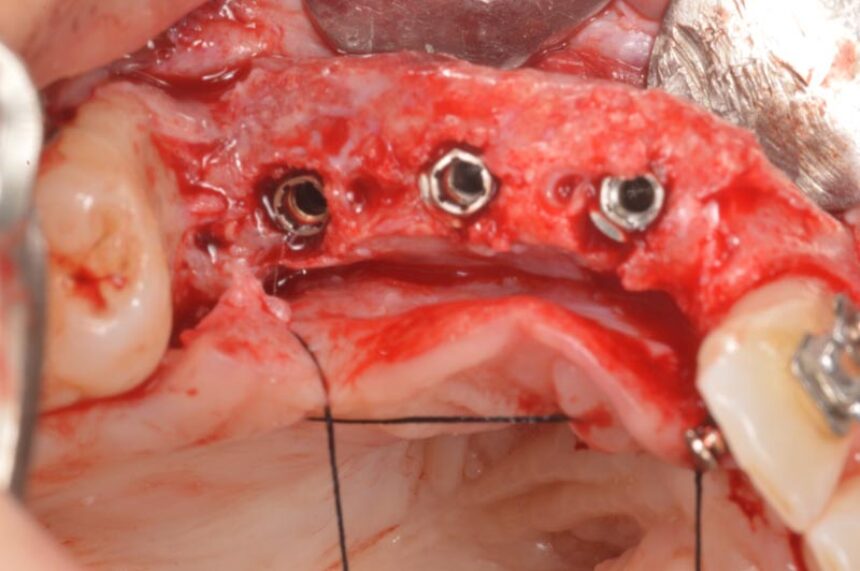

Πιο συγκεκριμένα, ο Prof. Massimo Simion, είναι ένας από τους πρωτεργάτες της διαδικασίας της Κατευθυνόμενης Οστικής Αναγέννησης στο χώρο της εμφυτευματολογίας. Μέσα από την τριαντακοετή εμπειρία του θα μας μεταφέρει τις εμπειρίες του στο χώρο αυτό καθώς και τα μυστικά επιτυχίας σε περιστατικά εκτενούς έλλειψης της φατνιακής ακρολοφίας τόσο στην άνω, όσο και στην κάτω γνάθο, αλλά και θα παρουσιάσει την αντιμετώπιση διαφόρων επιπλοκών που μπορεί να προκύψουν στην αντιμετώπιση αυτών των περιστατικών που αποτελούν πρόκληση για τους κλινικούς.

Οριζόντια και Κάθετη Αύξηση της Ακρολοφίας: χειρουργικό υπόβαθρο - χειρουργικές τεχνικές – απορροφήσιμες και μη-απορροφήσιμες μεμβράνες – λήψη οστικού μοσχεύματος από ενδο-στοματικά σημεία – βίντεο

Μακροπρόθεσμα αποτελέσματα μετά από 30 χρόνια εμπειρίας.

Αντιμετώπιση επιπλοκών της GBR.